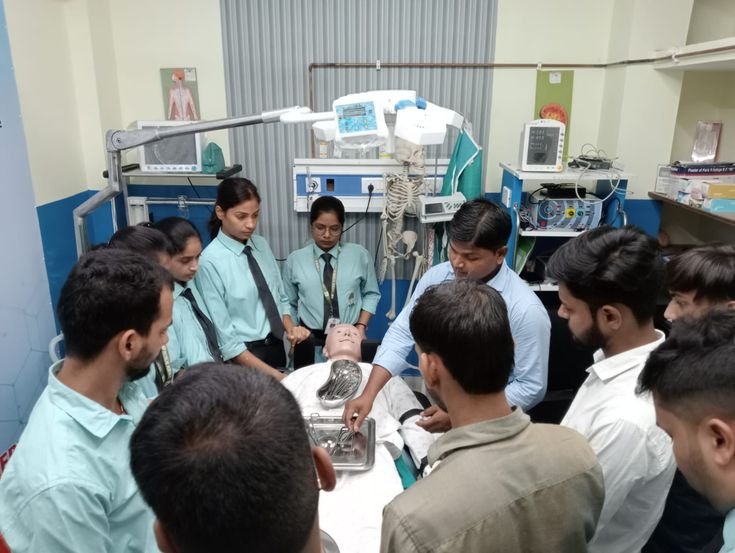

We offer a wide range of Paramedical and Nursing courses such as ANM, GNM, DMLT, X-Ray Technician, ICU Technician, OT Assistant, Dialysis Technician and more with practical hospital training.

Our institute focuses on skill-based education with modern labs, experienced faculty, and real-time hospital exposure to prepare students for a successful career in the healthcare industry.